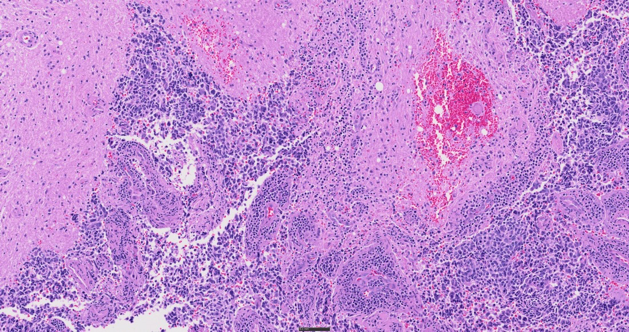

Voyez davantage de détails dans vos échantillons grâce à cinq modes d’imagerie – fond clair, lumière polarisée, fluorescence, fond noir et contraste de phase – et à la possibilité de combiner plusieurs techniques en une seule numérisation. Cette flexibilité ouvre la porte à de multiples possibilités pour l’observation d’échantillons d’histologie et de cytologie, allant de l’anatomopathologie de routine à la caractérisation moléculaire avancée de tissus cancéreux.

CD3 d’amygdale (rm), anti-IgG de souris (réactif ImmPRESS [PR]) + substrat Immpact DAB (brun), anticorps AE1/AE3 (m) + anti-IgG de lapin (ImmPRESS [PA] [PR]) + substrat Immpact Vector Red (rouge). Contre-coloration à l’hématoxyline QS (bleue).

Données d’images reproduites avec l’aimable autorisation de Vector Labs.